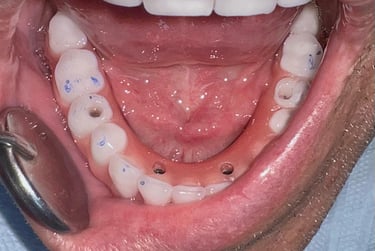

Técnica de Cirurgia Guiada para Implantes

A cirurgia guiada utiliza planejamento digital e guias cirúrgicos impressos em 3D, oferecendo maior precisão, menor tempo de cirurgia e recuperação mais confortável.

Pouco osso? A cirurgia guiada pode ser a solução.

Mesmo quando há pouca quantidade de osso, muitas vezes não é preciso fazer enxerto.

Com o uso de tecnologia digital em 3D, a cirurgia guiada permite planejar com precisão milimétrica a posição dos implantes, aproveitando ao máximo o osso disponível.

Esse planejamento detalhado também possibilita desviar de estruturas importantes, como o canal mandibular (por onde passa um nervo sensível) e o seio maxilar (uma cavidade natural próxima aos dentes superiores), tornando o procedimento mais seguro e previsível.

O resultado? Cirurgias mais rápidas, com recuperação mais tranquila e excelentes resultados — mesmo em casos que antes pareciam difíceis.

Caso da cirurgia guiada dispensando o enxerto - Imagens originais — nenhuma contém retoques